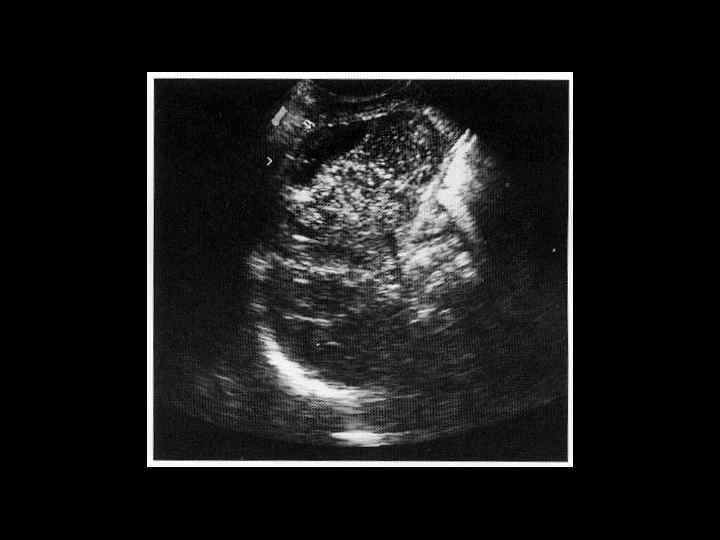

АКТУАЛЬНЫЕ ВОПРОСЫ РЕНТГЕНОЛОГИИ ЛУЧЕВАЯ ДИАГНОСТИКА ЗАБОЛЕВАНИЙ СЕЛЕЗЕНКИ Травма и инфаркт селезенки